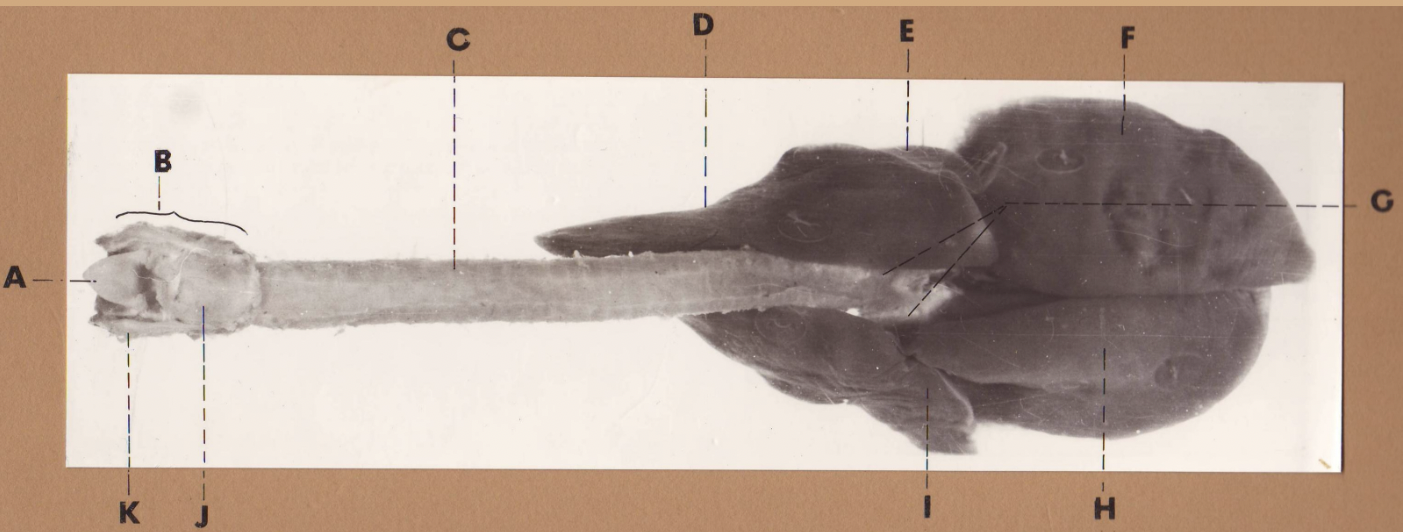

A

(pig lungs, dorsal)

L cranial lobe, caudal segment

B

(pig lungs, dorsal)

L cranial lobe, cranial segment

C

(pig lungs, dorsal)

trachea

D

(pig lungs, dorsal)

R cranial lobe

E

(pig lungs, dorsal)

cardiac notch

F

(pig lungs, dorsal)

middle lobe

G

(pig lungs, dorsal)

dorsal border

H

(pig lungs, dorsal)

costal surface

I

(pig lungs, dorsal)

basal border

J

(pig lungs, dorsal)

R caudal lobe

K

(pig lungs, dorsal)

L caudal lobe